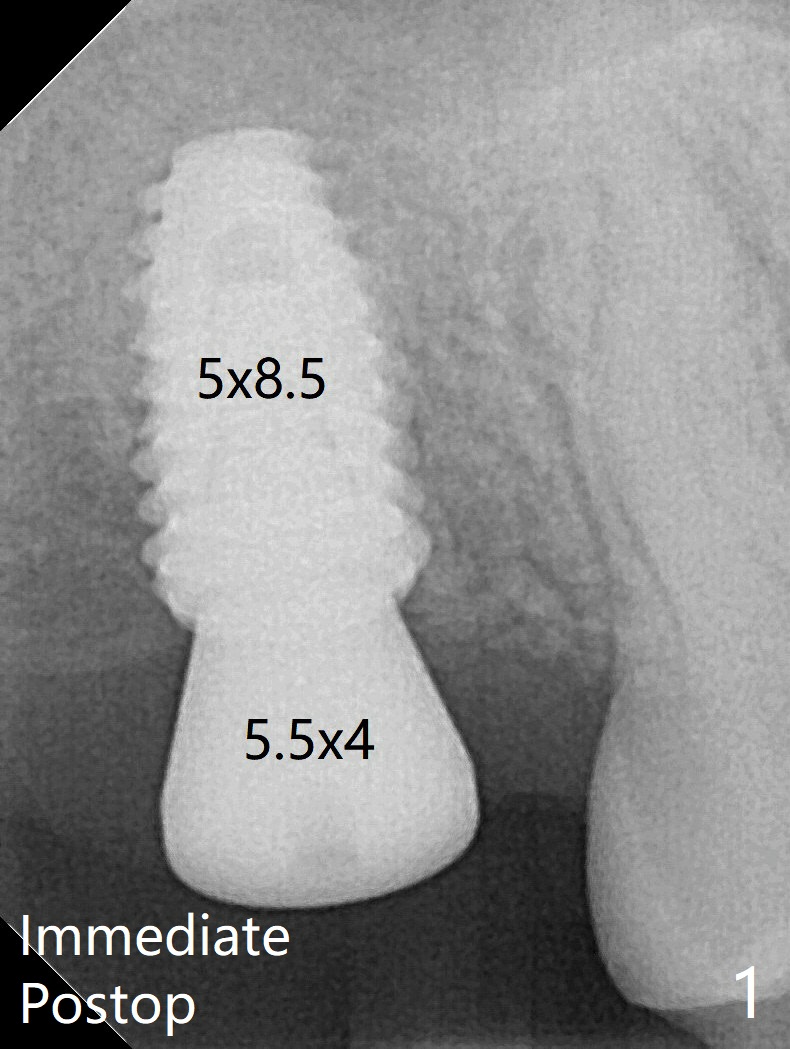

In spite of underprep (4.0x8.5 mm last drill), a 5x8.5 mm implant is placed at #2 with insertion torque ~ 15 Ncm (Fig.1). In addition to the large defect post implant removal with 4.5 month bone graft, he is a heavy gagger with limited mouth opening. Drill cylinders may not engage the metal sleeve precisely. A 5.5x4 mm healing abutment is placed with low emergency profile. PA taken 1 month postop shows slightly subcrestal placement (Fig.2). When a cemented abutment is placed 4 months postop, there is tenderness. In fact the implant is mobile. A 8x5 mm healing abutment is placed. Nine months postop, the implant remains slightly mobile (Fig.3); a healing screw is placed. Low Torque Last Next Xin Wei, DDS, PhD, MS 1st edition 11/27/2018, last revision 12/16/2019